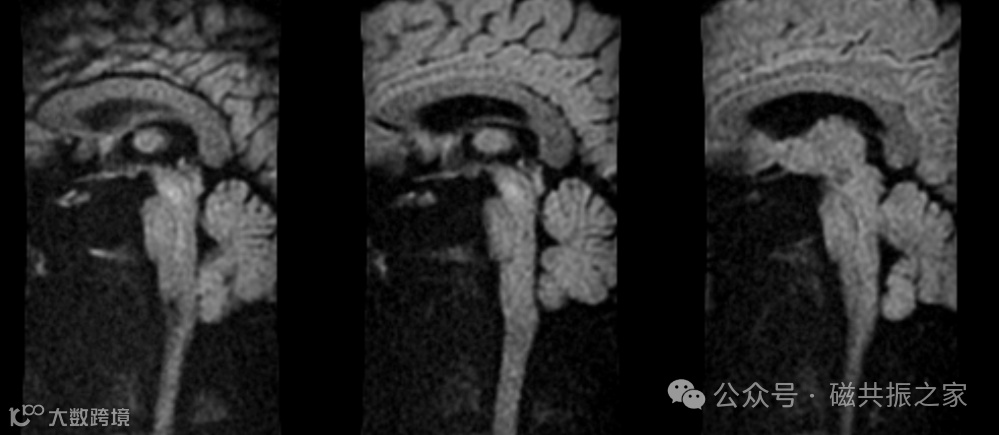

如在评估关节软骨及细微结构时,需要关注的重点则是如何保留更丰富的对比信息,减少模糊伪影,则建议使用高带宽来减小回波间隙,以达到改善模糊效应保证细节对比的目的。

实际扫描中会涉及到很多改善磁敏感伪影和运动伪影的技术,在应用这些技术时不宜采用过窄的带宽。如在使用抗运动伪影的螺旋桨/风车/刀锋序列来改善其伪影时建议采用高带宽。